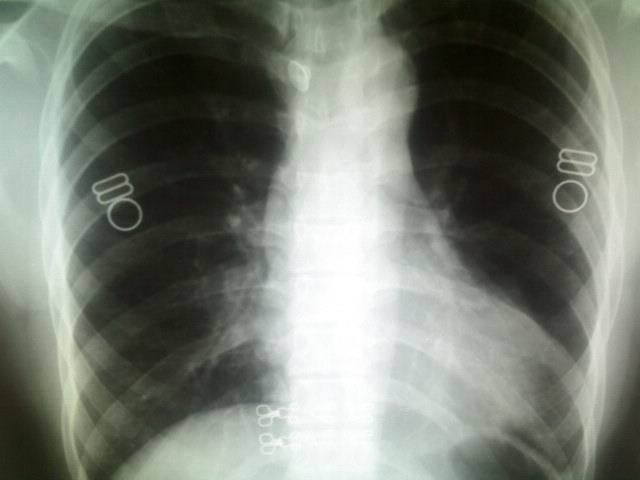

标题: X5295:大家看看,是肺上病变还是心脏上的。

女,23岁,体检。

室壁瘤?肺部占位?肺疝?建议侧位片或ct检查。

哪里?是心尖部吗?应该是心脏与肋骨、乳房的重叠形成的构成影。心右缘肺野密度增高,考虑肺心动脉,不除外肺部病变,建议侧位或ct

考虑左下肺病变;建议行ct扫描检查。

透视下,病灶随心脏搏动,外缘不光整。